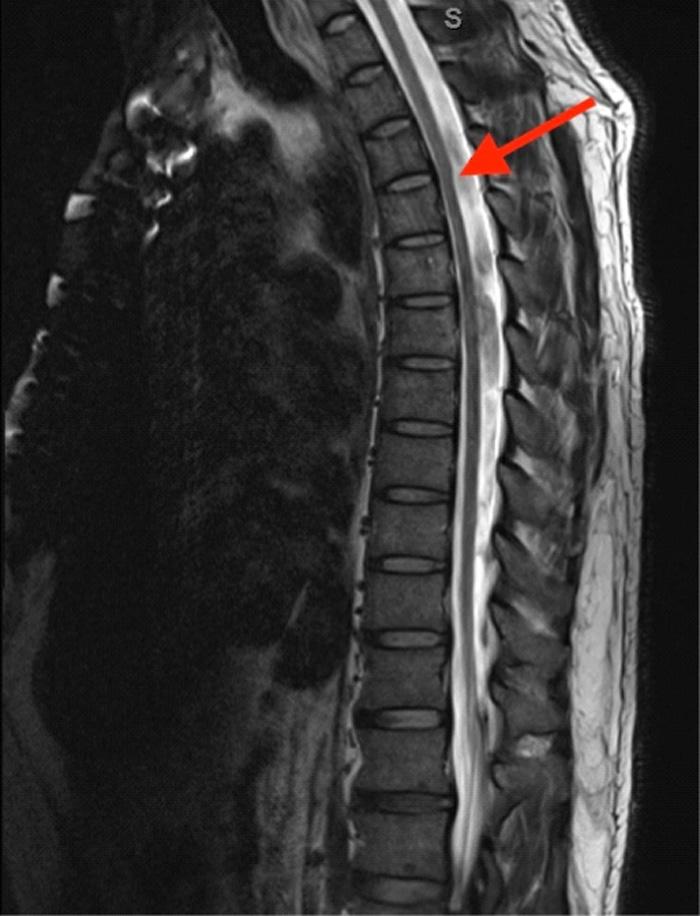

300 Spinal Arachnoid Web

Maiya Smith, Morgan Ketterling, Alexander Gallaer, Rowan Kelner, Christine Raps, Allison M. Beaulieu